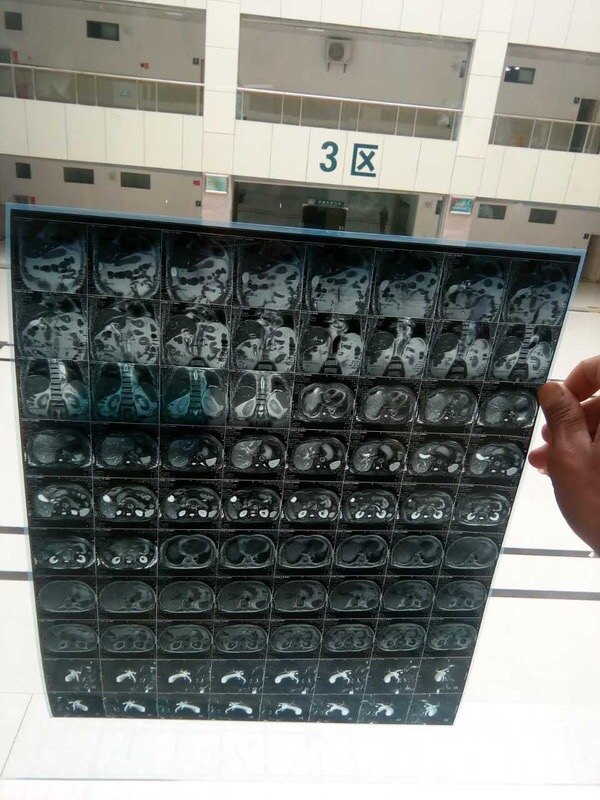

如何正确的把拍的片子发给医生看!

一般的报告就不再说了,正常拍摄就可以,我说的是片子应该怎么拍,一般是1-4小张拍一次,如下图:

下面看看直接无法直视的!